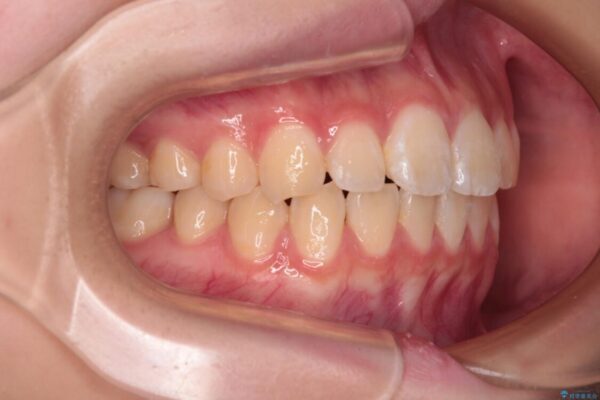

上下前歯のねじれを気にして来院された患者様です。

ワイヤー矯正でもマウスピース矯正でも対応可能でしたが、マウスピース矯正の自己管理が面倒であること、上顎前歯の捻転が著しいことから、ワイヤー矯正での治療を希望されました。

治療前

• インビザラインは使える自信がない ワイヤー装置にて矯正治療 治療前画像